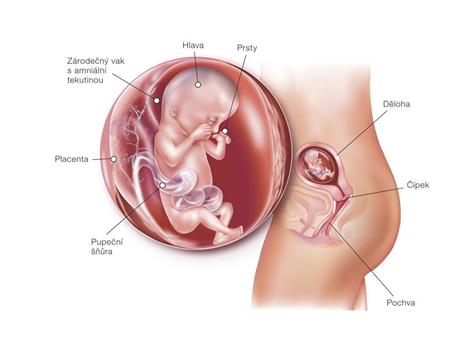

Při druhém pokusu jsme se s doktorkou dohodly, že nastoupím na dlouhý protokol, aby se mi vytvořilo víc kvalitních vajíček. Začala jsem stimulovat od půlky února a koncem dubna šla na odběr folikulů. A taky že to pomohlo, vytvořilo se víc kvalitních vajíček. V Sanatoriu jsem řekla embryologovi, jaký jsem měla posledně problém, a sama mi nabídla, že teda necháme PK na 5 dnů, aby viděli, jak se vyvýjejí a jak to zvládají. 1.5.2010 jsme si jeli do Prahy pro naše embroušky, dokonce vydrželi ještě další dva, které mi dali zamrazit do zálohy.